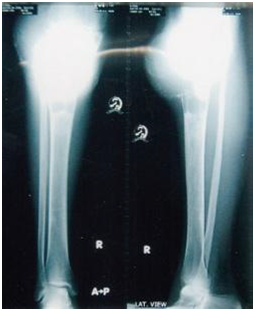

Figure 8 Radiographic view after 3 months follow up.

Figure 9 Final radiographic view of upper tibia with full consolidation after 6 months